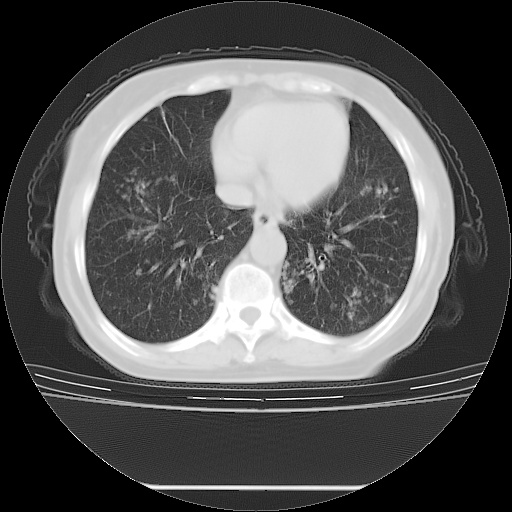

患者女性,72岁,慢性咳嗽3月余,曾抗炎治疗无效果,最近抗结核治疗约半月余,症状缓解。

ct示两肺粟粒状病灶,以两肺上叶尖后段及下叶背段分布为主;首先考虑结核。请战友们分析。

考虑 1 弥漫性泛细支气管炎, 2 结核不除外/.  有小叶中心结节 和 树芽征!!

两肺内病灶呈小结节状和树芽状,纵膈的肿大的淋巴结密度不均匀,并见有钙化,考虑为两肺结核可能更大些。

两肺内病灶呈小结节状和树芽状,纵膈的肿大的淋巴结密度不均匀,并见有钙化,多形态病灶,考虑为两肺结核,肝内考虑小囊肿。

片子很好,质量很高,两侧肺门淋巴结肿大并有钙化,两肺弥漫病灶,首先考虑tb并播散,但年龄大了呀(72岁)小细胞肺癌不能除外,如果是肺癌也没什么大的治疗了,建议正规抗结核治疗后复查

两肺内病灶呈小结节状和树芽状,纵膈的肿大的淋巴结密度不均匀,并见有钙化,结合(曾抗炎治疗无效果,最近抗结核治疗约半月余,症状缓解。)

考虑为两肺结核可能更大些。